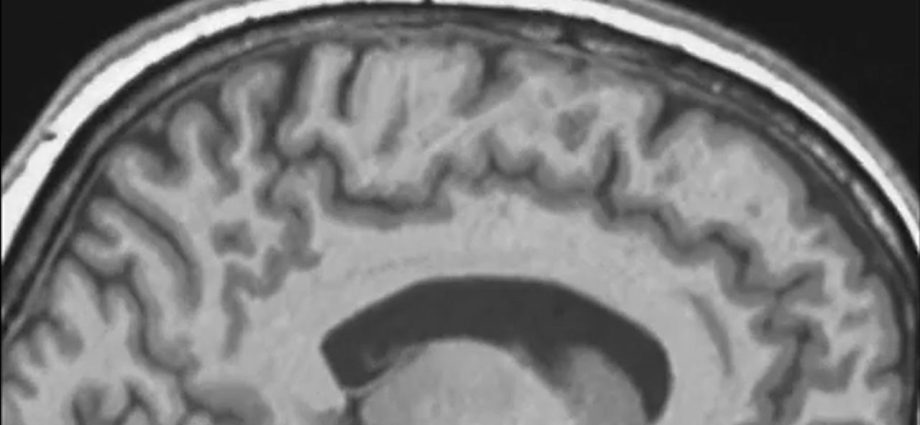

‘Backward and upward and tilted’: Spaceflight causes astronauts’ brains to shift inside their skulls

What effects do spaceflight have on the astronaut brain? (Image credit: Wang, Odor, et al.) Spaceflight doesn’t just change your perspective — it shifts the actual position of your brain inside your skull, a new study reports. Many of us know about the famed ” overview effect, ” which describes how a trip to theContinue Reading